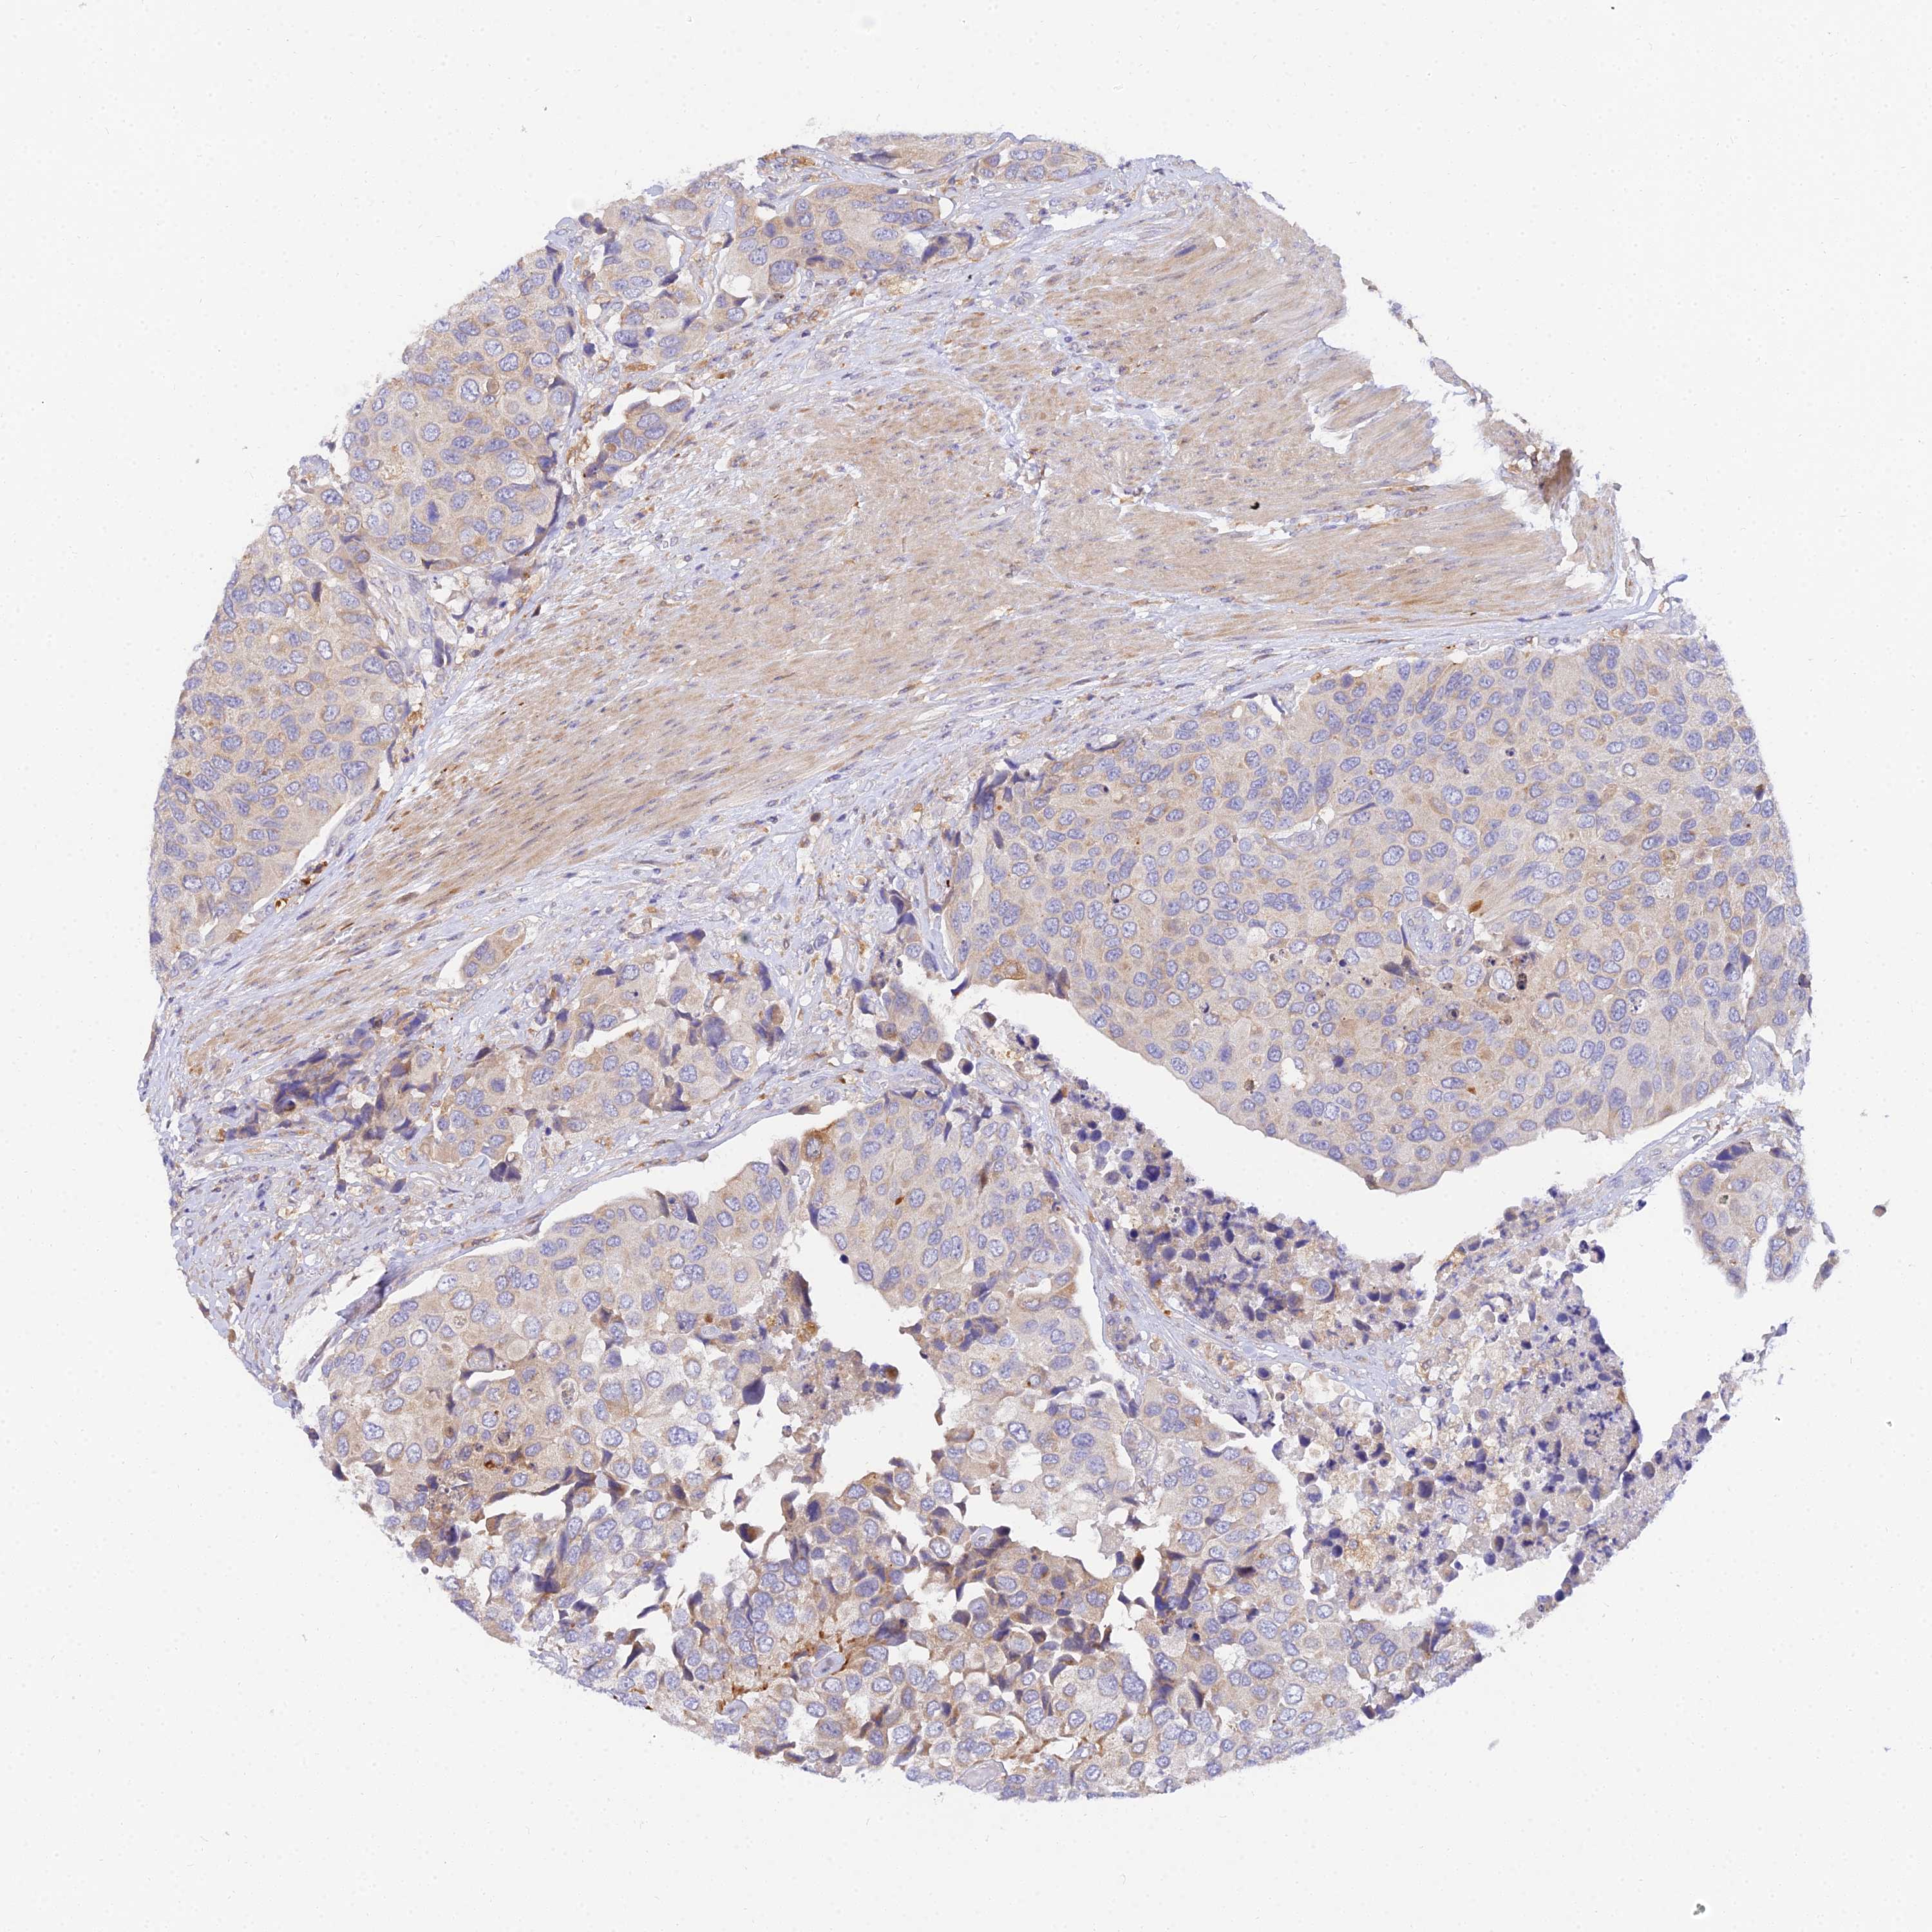

UROTHELIAL CANCER - Protein expressioni

A mouse-over function shows sample information and annotation data. Click on an image to view it in a full screen mode. Samples can be filtered based on level of antibody staining by selecting one or several of the following categories: high, medium, low and not detected. The assay and annotation is described here.

Note that samples used for immunohistochemistry by the Human Protein Atlas do not correspond to samples in the TCGA dataset.

Antibody stainingi

Antibody staining in the annotated cell types in the current human tissue is reported as not detected, low, medium, or high, based on conventional immunohistochemistry profiling in selected tissues. This score is based on the combination of the staining intensity and fraction of stained cells.

Each image is clickable and will lead to virtual microscopy that enables deeper exploration of all samples and also displays staining intensity scores, fraction scores and subcellular localization as well as patient and tissue information for each sample.

Antibody HPA038759

Antibody HPA040515

Antibody HPA045924

Urothelial carcinoma, High grade

Urothelial carcinoma, Low grade